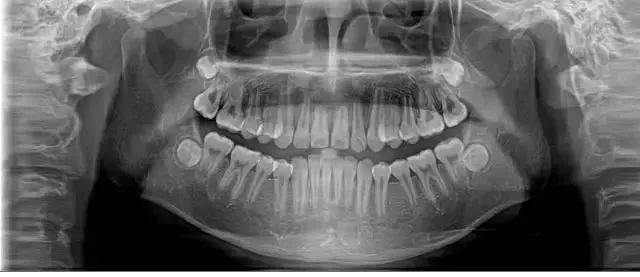

醫(yī)生經(jīng)過系統(tǒng)檢查后,確定這位年輕人出現(xiàn)全口多處牙齒的松動(dòng),診斷為侵襲性牙周炎。

經(jīng)過口腔醫(yī)院診斷,她患上了嚴(yán)重的牙周炎,醫(yī)生先后為其拔除了11顆牙齒,并種植了10顆牙齒。

28歲的小孟因刷牙時(shí)突然一顆門牙脫落,當(dāng)她到醫(yī)院就診時(shí),醫(yī)生告訴她上排牙已全部不能保留。

小孟的牙齒已經(jīng)出現(xiàn)了不同程度的松動(dòng),而導(dǎo)致她松動(dòng)至功能喪失的是嚴(yán)重的牙周炎。終只能將其牙拔去后,花費(fèi)十五六萬元選擇種植牙。

一旦出現(xiàn)牙周炎,會(huì)導(dǎo)致牙周支持組織的炎癥、牙周袋形成、進(jìn)行性附著喪失和牙槽骨吸收,后嚴(yán)重的情況下會(huì)導(dǎo)致牙齒松動(dòng)而被移除。

湯俊嶺介紹,牙周炎分為慢性牙周炎和侵蝕性牙周炎。年輕人掉牙的上述案例就是屬于侵蝕性牙周炎,多發(fā)生在20~30歲之間的患者中。